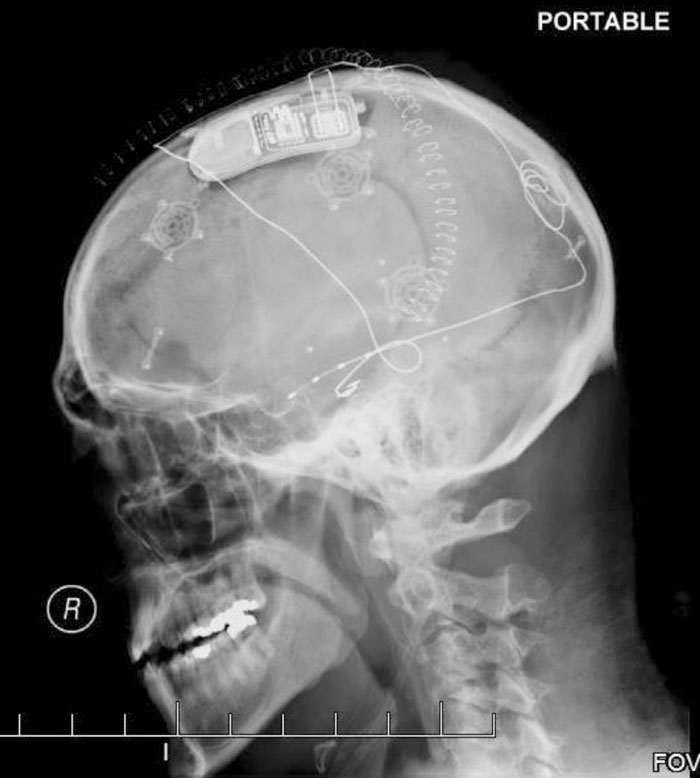

Устройство для электростимуляции мозга, блокирующее припадки